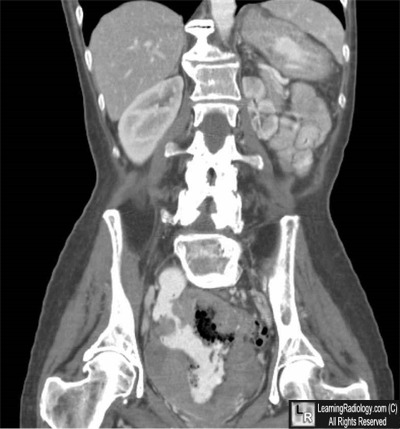

Coronal Reconstruction of CT of Abdomen and Pelvis

5. Small Bowel Lymphoma

Small Bowel Lymphoma